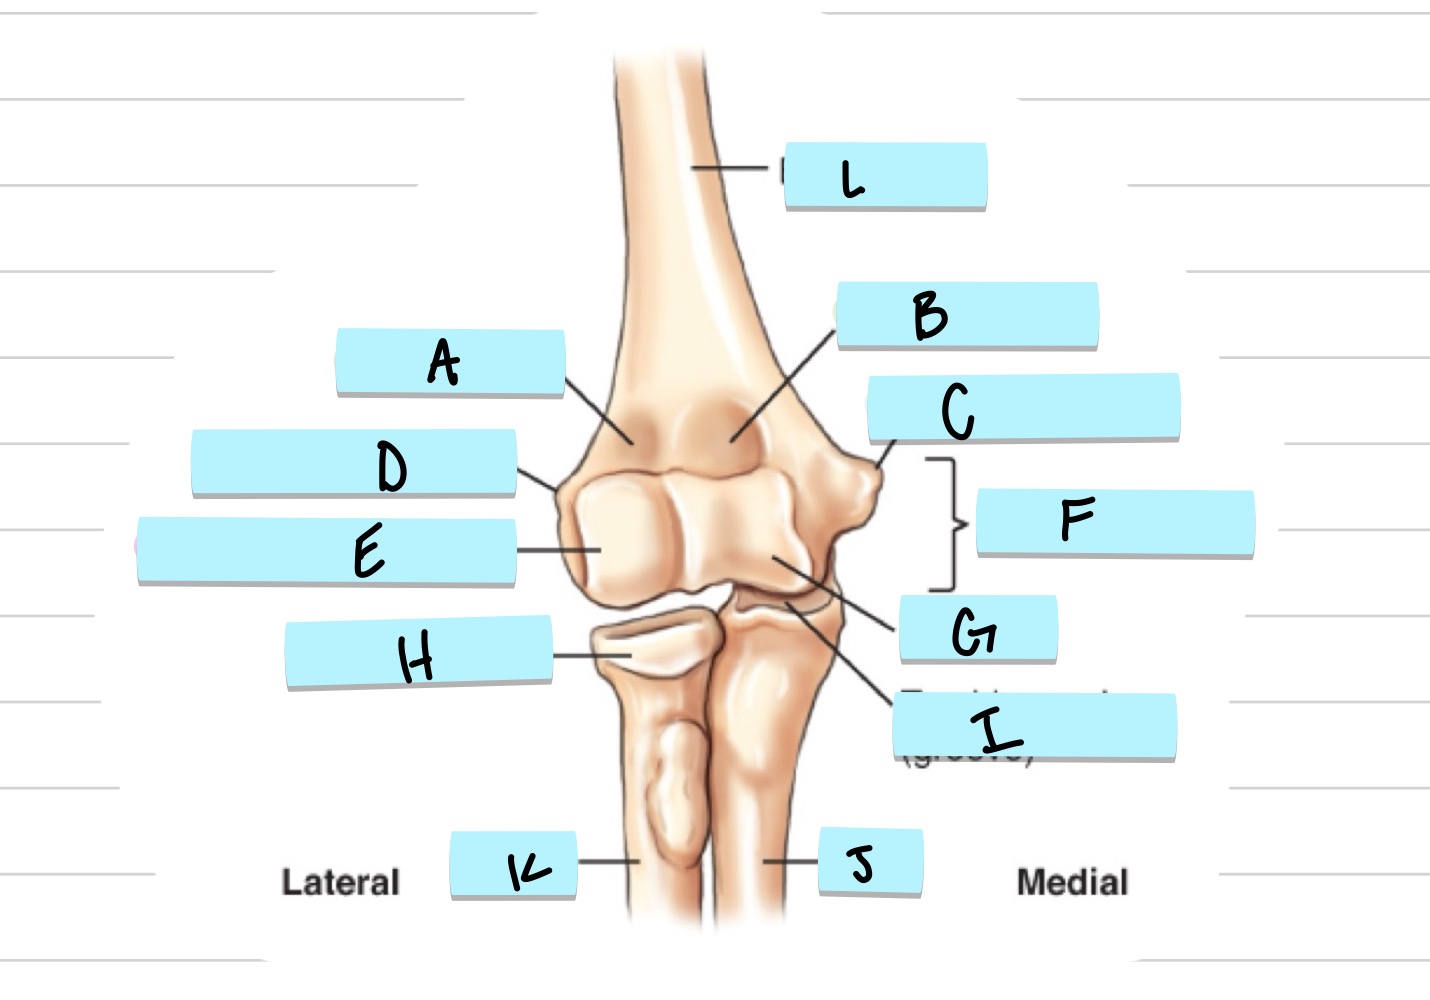

<p>what is A?</p>

what is A?

radial fossa

83

New cards

<p>what is B?</p>

what is B?

coronoid fossa

84

olecranon process

36

trochlear notch

37

<p>what is C?</p>

what is C?

coronoid process

38

<p>what is D?</p>

what is D?

radial notch